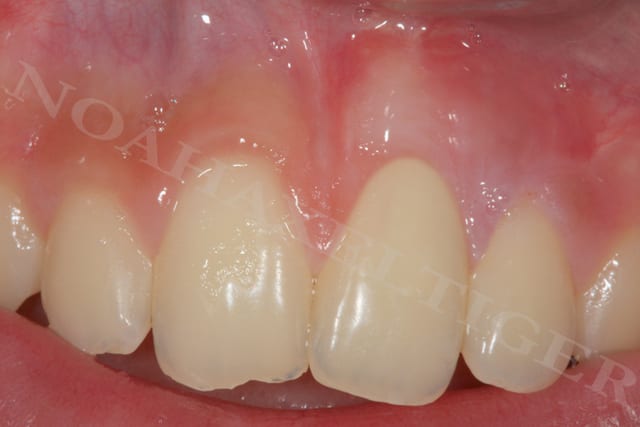

lors de la cicatrisation on remarque une amélioration gingivale au niveau de 32 et 42 mais malheureusement une récession persistante au niveau de 31 et surtout 41.

Lors de l'analyse des différents facteurs de cicatrisation, je note alors que 31 et surtout 41 sont mobiles grade 1 !!

Du coup, controle occlusal, contention et opération numero 2 (date de la semaine dernière) :